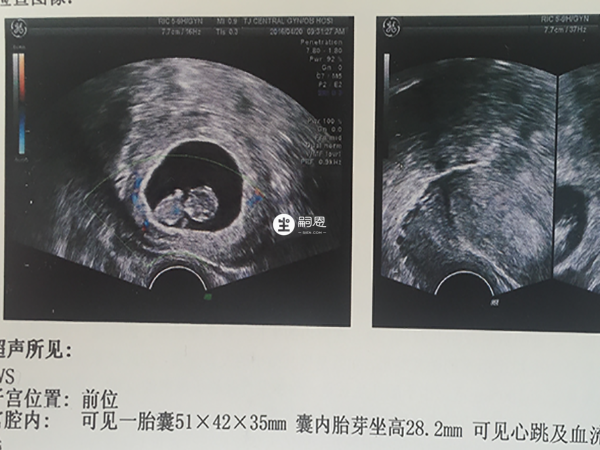

胎囊是立體的圓形或橢圓形的胚胎組織,月經週期規律的孕婦,最早可在停經35天時通過B超看到宮腔內圓形或橢圓形的胎囊,妊娠6周時,還可以看到胎芽、胎心,也可以根據胎囊的大小來核對懷孕天數,網路上流傳著不少胎囊看男女的方法,下面就分享一下具體說法:

B超單子上不僅會附上胎囊的圖片,還會顯示出胎囊的詳細資料,如果發現兩條邊長之和是第三條邊長的兩倍以上,如4.0cm*3.8cm*1.9cm,則大概率是男孩,反之如果三條邊長數值接近,比如2.9cm*1.8cm*1.8cm,則可能是女孩。

不同孕周胎囊大小是會發生變化的,根據一些寶媽的經驗總結,7周時若胎囊大小在20*19*19左右則可能是女寶,同樣7周,若胎囊大小在20*40*20左右則是男寶,孕8周左右30*30*20是女寶,資料為40*40*20則是男寶。

胎囊也就是孕囊,其三個資料分別對應長、寬、厚的數值,臨床上還可以利用孕囊大小推斷預產期,懷孕天數=孕囊平均直徑+30天,根據此方法計算出女性懷孕天數,進而推算出預產期,此外,不少寶媽在孕初期都會利於孕囊來看寶寶男女,下面就分享一下其他寶媽的經驗:

彩超觀察胎囊的大小、形態、位置,是判斷妊娠是否正常的重要依據,但從胎囊的形態無法判斷胎兒的性別,一般要到妊娠4個月左右,胎兒的生殖器才初見雛形,下面還整理了一些有關胎囊看男女的相關問題及解答:

胎囊和胎兒性別之間沒有明確關係,超聲發現宮內胎囊或胚芽可明確宮內妊娠,如果有原始心管搏動則提示胚胎存活,因此,超聲發現胎囊是確診正常早期妊娠的重要指標,超聲檢查所見胎囊形態,與妊娠時間、超聲檢測方位等多種因素有關,與性別沒有明確關係,不能通過胎囊判斷胎兒性別。